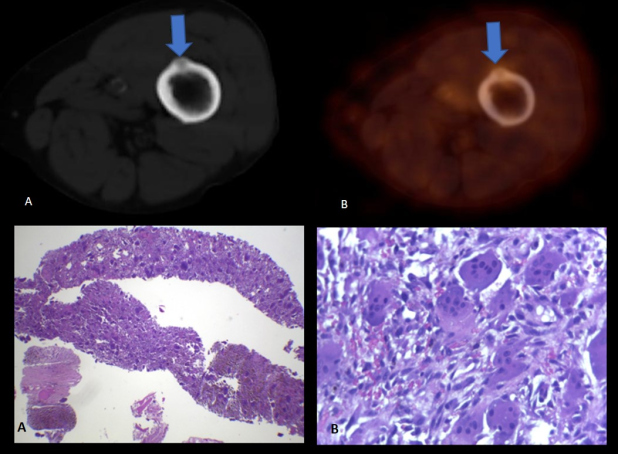

A raíz del hallazgo tomográfico y por sospecha de patología oncológica se solicita PET- CT con fluorodesoxiglucosa (18F-FDG), donde se advierten múltiples lesiones óseas líticas hipermetabólicas (algunas con erosión de la cortical), incluyendo un foco esternal con SUV máx. 8,4, otra en el 7° arco costal derecho (fig. 1) y una tercera imagen focal con insuflación cortical, densidad en vidrio esmerilado en su interior ubicada en tercio medio femoral (fig. 2, arriba), con algunos otros focos hipermetabólicos sin traducción tomográfica. También se evidencia a nivel submaxilar derecho una lesión con densidad de partes blandas, con captación aumentada (SUV máx. 4,2) y centro fotopénico en relación a necrosis.

La 18F-FDG es un radiotrazador que permite analizar el metabolismo energético de la lesión en estudio; representa un marcador imagenológico inespecífico, ya que puede ser captado con tanta avidez por una lesión oncológica como por una patología inflamatoria. Solamente indica aumento de metabolismo de glucosa y no informa sobre su etiología, la cual debe ser valorada en un contexto clínico-morfo-metabólico y certificada con estudio anatomopatológico. (3) En este caso, la interpretación clínica del PET-CT con FDG fue que la formación submaxilar estaba en relación a compromiso inflamatorio/infeccioso derivado del procedimiento quirúrgico odontológico reciente, descartando una posible patología oncológica linfo-proliferativa. Se llegó a la conclusión preliminar de que las lesiones óseas formaban parte de un proceso osteodistrófico debido a la patología renal crónica de base. Esto condujo a la toma de biopsia con confirmación histopatológica de la lesión en el 7° arco costal posterior izquierdo, donde se halló evidencia compatible con tumor pardo (fig. 2, abajo).